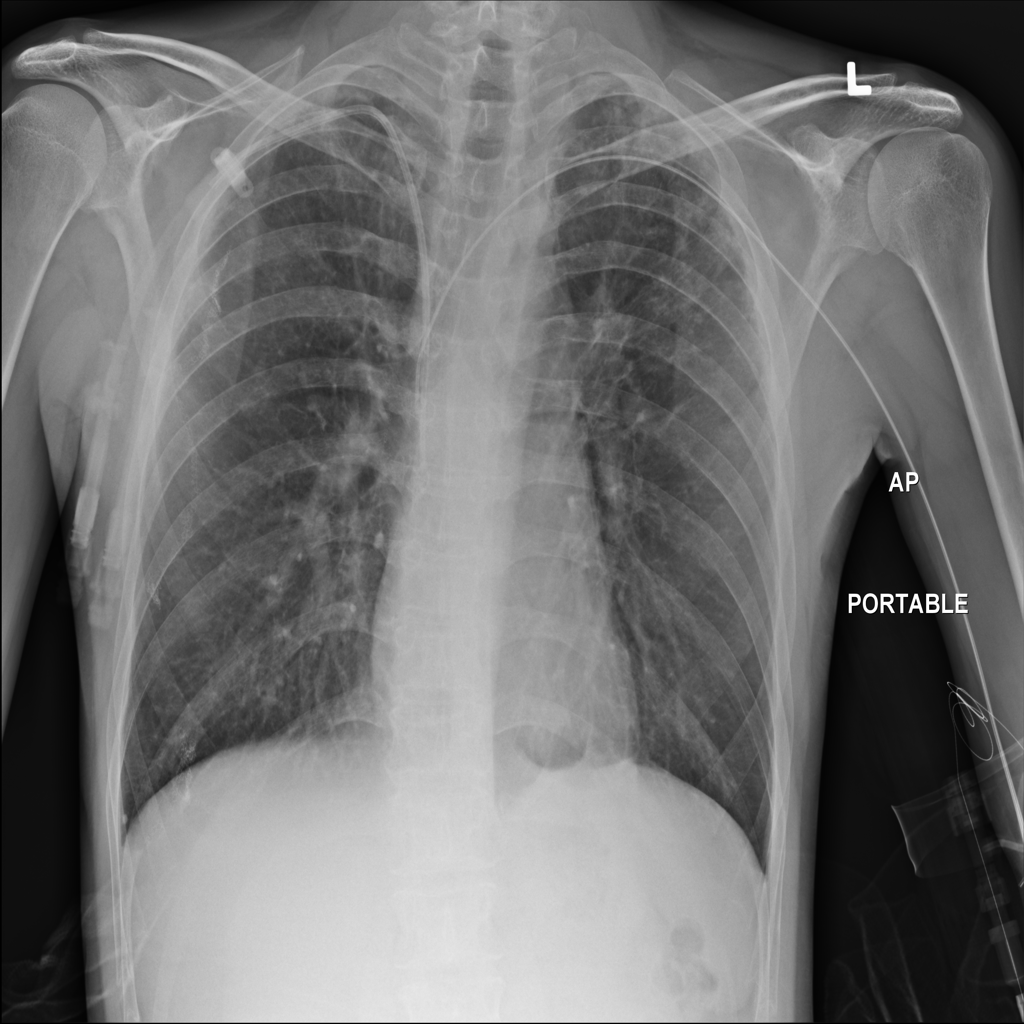

PAT-988D · IMG-001Nodule

PAT-988D · IMG-001

AP